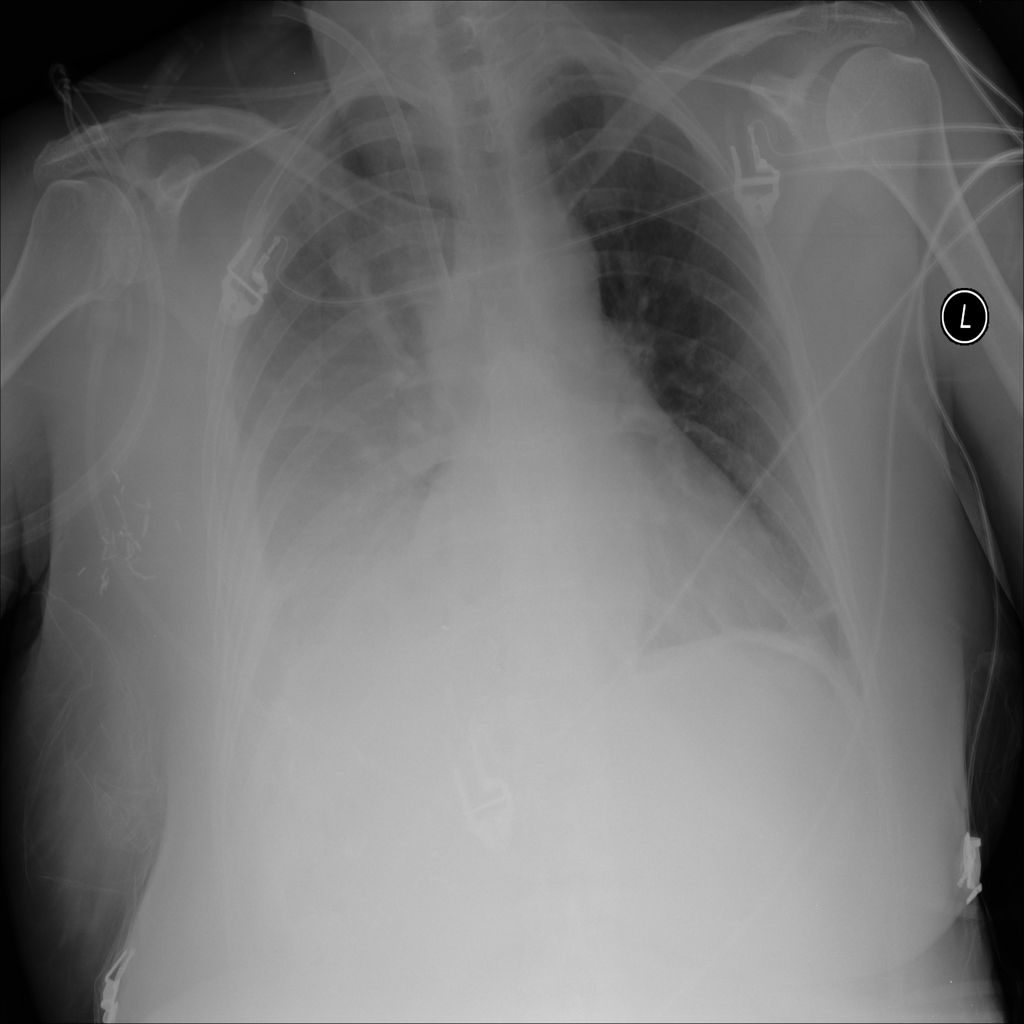

Pleural Effusion

Pleural effusion means extra fluid has collected around the lung in the pleural space. It can happen with heart problems, infection, inflammation, or other underlying conditions.

Showing up to 90 reference images for Effusion.

PAT-2519 · IMG-018Effusion

PAT-2519 · IMG-018

AP